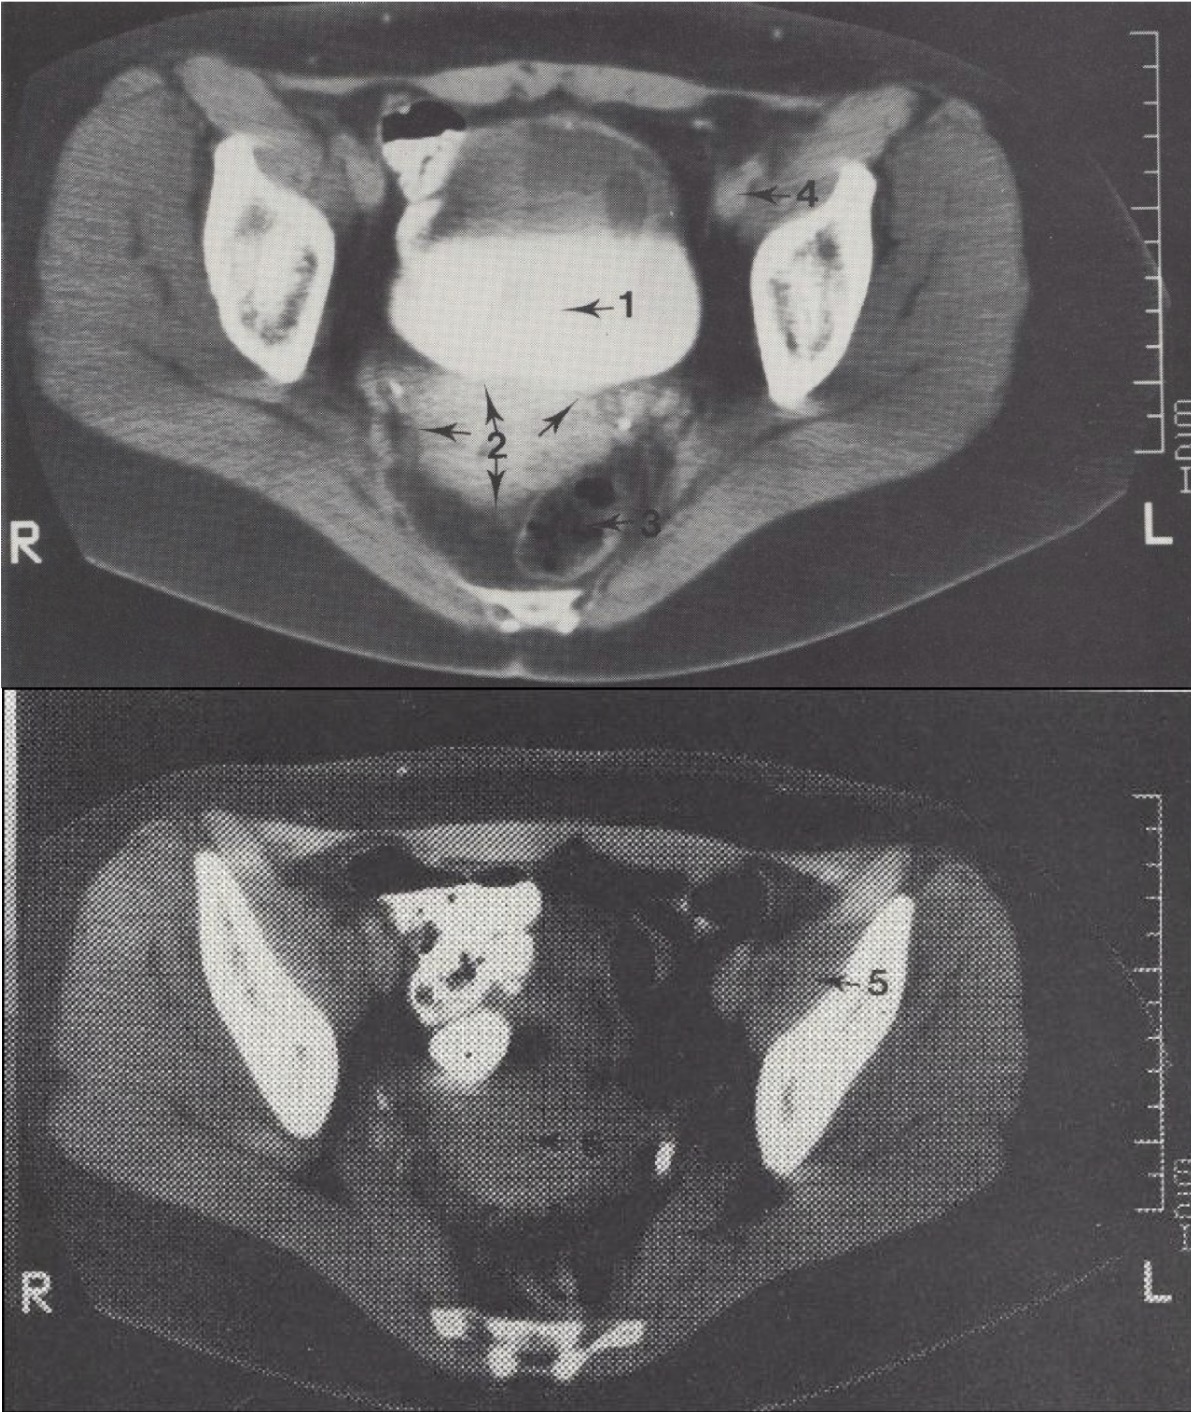

1

Vesica urinaria (šlapimo pūslė)

2

Corpus uteri (gimdos kūnas)

3

Rectum (tiesioji žarna)

4

A. et v. iliaca externa (išorinė klubo arterija ir vena)

Metodika

KT pjūviai atlikti virš acetabulum (gūžduobės). Naudotas intraveninis kontrastas (šlapimo takams) ir peroralinis kontrastas (žarnyno kilpoms).

Svarbu

Pacientei gulint, šlapimo pūslėje matomas kontrasto išsisluoksniavimas: sunkesnis jodo kontrastas nusėda apačioje, o lengvesnis šlapimas – viršuje.

Topografija

Gimdos šešėlis (corpus uteri) matomas tarp tiesiosios žarnos (rectum) ir šlapimo pūslės (vesica urinaria).